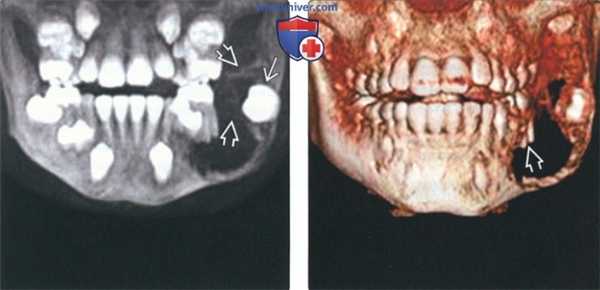

(Слева) На панорамной реформатированной КЛКТ определяется крупная АФ в задних отделах нижней челюсти, связанная с коронкой формирующеюся непрорезавшегося второго постоянного моляра АФ, содержащая перегородки, выбухает в задние отделы ветви.

(Справа) На трехмерной реконструкции (вид спереди) у этого же пациента визуализируются корни постоянного первого моляра нижней челюсти слева в АФ.